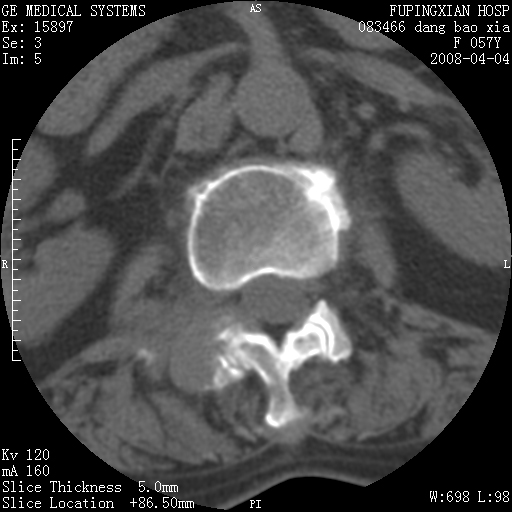

标题: CT12677:女性,57岁,疼痛数月。 [打印本页]

标题: CT12677:女性,57岁,疼痛数月。

椎体及附件骨质破坏同时伴软组织肿块,首先考虑恶性肿瘤。

椎体及附件骨质破坏,伴软组织肿块,首先考虑恶性骨肿瘤,建议提供正侧位片。

骨组织起源,膨胀,软组织肿块=恶性改变:首选骨巨,其次转移瘤,再次脊索瘤

椎体及附件溶骨性破坏,周围巨大软组织肿块,首先考虑转移瘤。